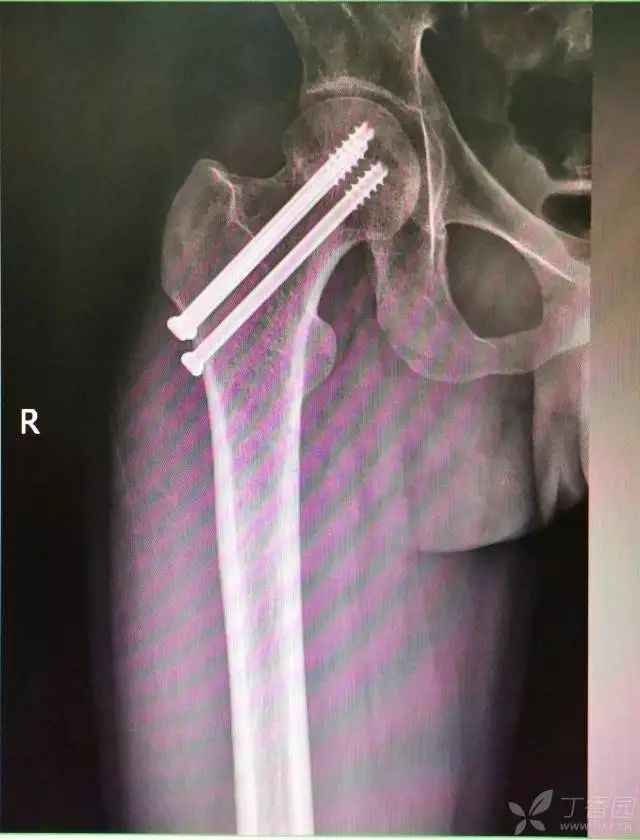

4. 先体外放置一枚导针导引进针方向

5. 打入第一枚倒品字下方导针,跟体外导针基本重叠

6. 然后依次打入倒品字上方的两枚导针

7. 摆 4 字位检查侧位导针的位置是否恰当

打入第一枚导针时应非常小心,一定是要和体外的导针保持方向一致。还有一个小细节是,进针前笔者一定会体外先摸股骨大粗隆的外侧,判断前后位置,进第一枚导针到达股骨外侧后,用针尖在股骨外侧面前后滑动,再次判断进针点是否居中。

第一枚导针一定要打好,进针一半时透视看看方向,如果不好,及时调整。笔者做股骨颈骨折有个体会,尽量一次性进针成功,反复穿针很容易导针滑入原道,既影响复位维持,也会使再次穿针愈加困难。

第一枚导针打好以后,根据该导针距离股骨颈下方的距离(如下图),确定上方两枚导针的距离,距离过近,会导致螺钉打架或者汇聚,过远则打不到股骨颈内。

打第 2、3 枚导针有个小技巧,首先用导向器套住第一枚导针判断合适的距离,以及上方两枚导针之间的距离,此时顺着导向器插入第 2 枚导针。

这里需要注意的是,不是沿着导向器直接打进去(这样往往打入的导针无法与第一枚导针平行,不好看),笔者会稍打进去一点能把针固定住就好,然后把导向器退出来,看体外针尾平行方向往里打。这样确实打出来的导针都比较平行。最后把第三枚导针按第二枚的步骤打进去就可以了。